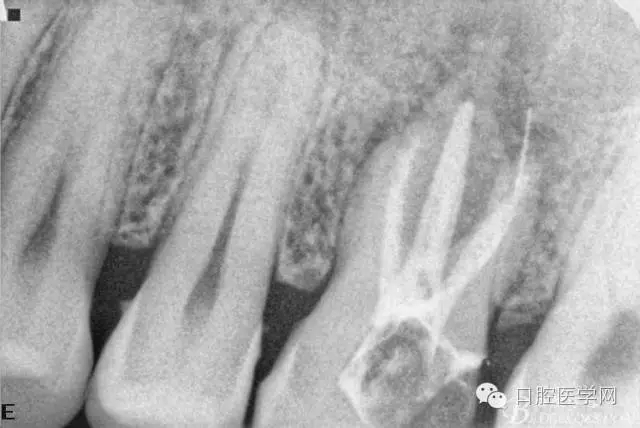

擴(kuò)根片(可惜遠(yuǎn)頰根有一斷針)